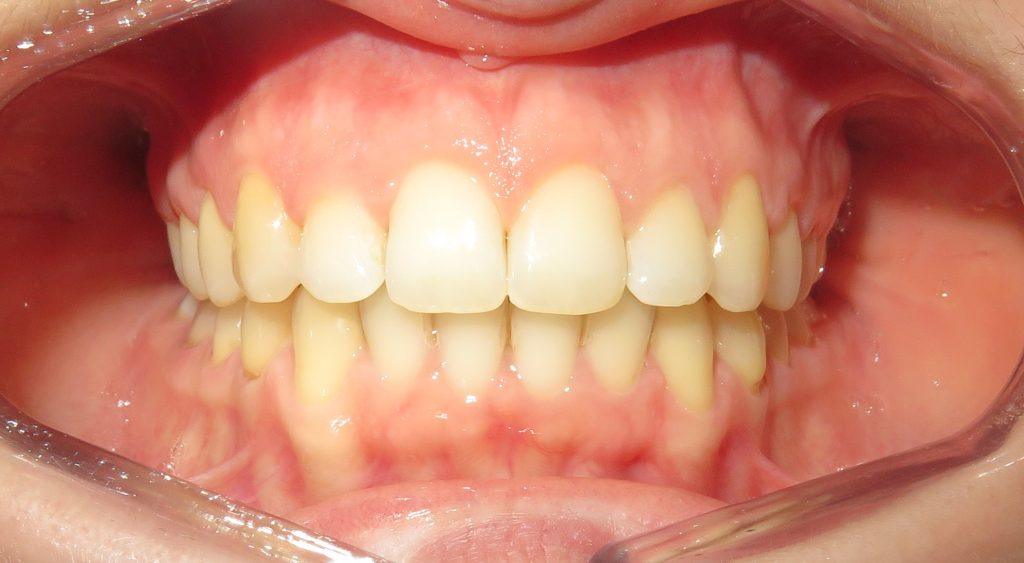

Pacjentka zgłosiła się do nas z takimi problemami, jak:

❌ zwężone łuki zębowe,

❌ tyłozgryz,

❌ głęboki zgryz,

❌ stłoczenia,

❌ zrotowane i starte zęby

Pod opieką Agnieszki Łukowicz, Master of Science Orthodontics została poddana zaawansowanemu leczeniu aparatem stałym ligaturowym, Dzięki czemu udało się osiągnąć znaczące zmiany:

✅poszerzenie luków zębowych,

✅korekta tyłozgryzu,

✅rozwiązanie stłoczenia,

✅odrotowanie zrotowanych zębów,

✅odbudowa startych zębów.

Efekt estetyczny został dopełniony przez wybielanie zębów i odbudowę kompozytową wykonaną przez dr Monikę Niewitecką.

Przedstawiamy piękny i zdrowy uśmiech naszej Pacjentki!